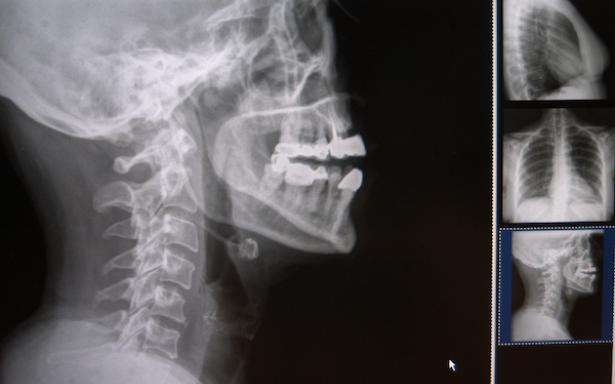

Explicó que la columna cervical se sitúa en el cuello, su función es contener y proteger la médula espinal, soportar el cráneo y permitir los diversos movimientos de la cabeza: rotarla de un lado al otro, inclinarla hacia adelante o atrás.

Al respecto, el doctor Jaime Castellanos Romero, director de la UMFR Siglo XXI refirió que en esta unidad se brinda atención a más de cinco mil 700 derechohabientes al año, donde el 10 por ciento de estos casos corresponden a problemas relacionados con la columna cervical.